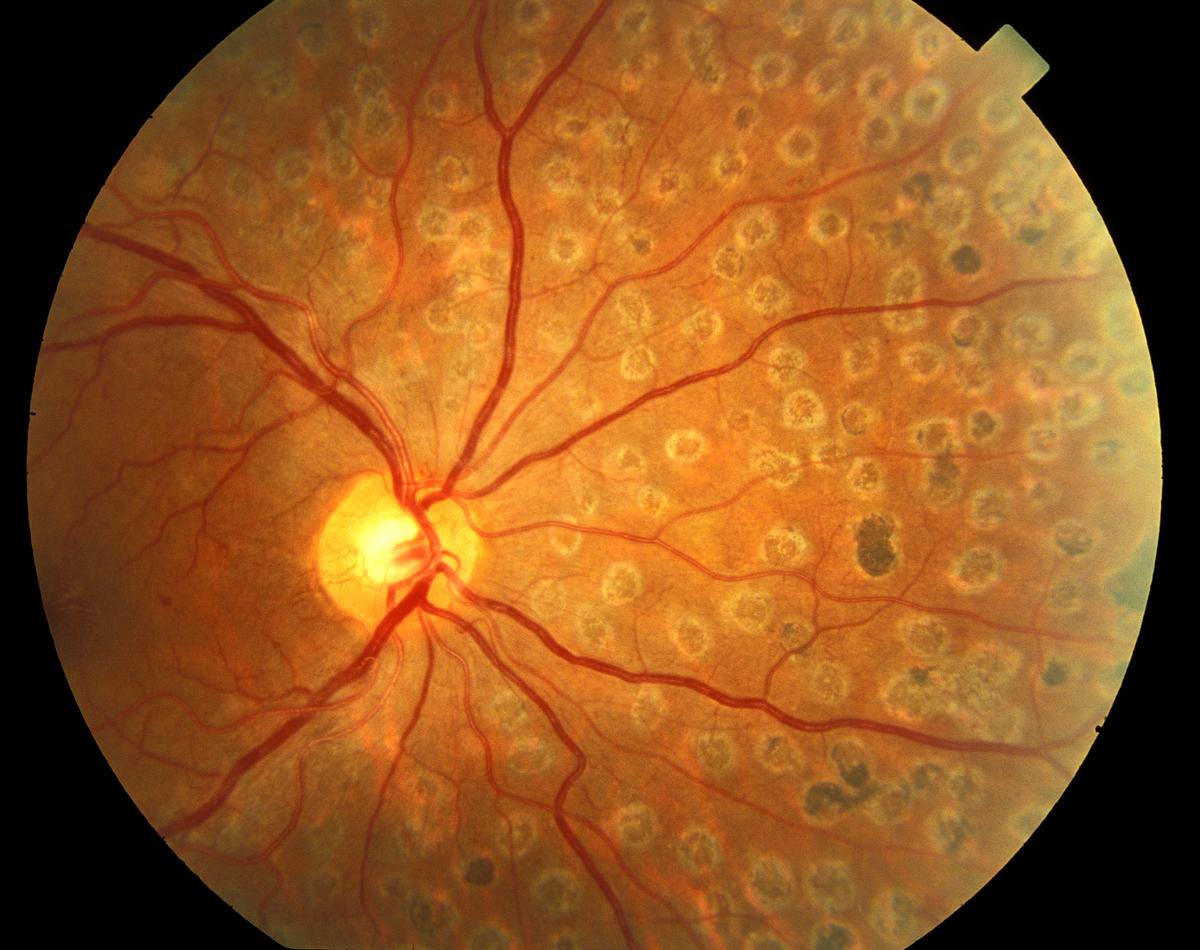

Изображения и анатомия сетчатки глаза

Раздел: Визуальный дайджест